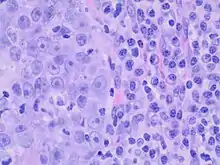

Medullary breast carcinoma is a rare type of breast cancer[1] that is characterized as a relatively circumscribed tumor [2] with pushing, rather than infiltrating, margins. It is histologically characterized as poorly differentiated cells with abundant cytoplasm and pleomorphic high grade vesicular nuclei.[3] It involves lymphocytic (a type of white blood cell) infiltration[4] in and around the tumor and can appear to be brown in appearance with necrosis and hemorrhage.[5] Prognosis is measured through staging but can often be treated successfully and has a better prognosis than other infiltrating breast carcinomas.

Criteria must be met through the Ridolfi criteria. Although there are other classifications for diagnosis, the Ridolfi criteria are the most commonly used. There must be histologic evidence of lymphoplasmacytic infiltration, noninvasive microscopic circumscription, greater than 75% syncytial growth pattern, and high-grade nuclei.[5] It is immunologically typically triple-negative, with negative estrogen receptors (ER), negative progesterone receptors (PR), and negative HER2/neu receptors.[3] There are also medullary breast carcinomas that are found to be estrogen receptors (ER) and/or progesterone receptor (PR) positive, making diagnosis less straightforward.